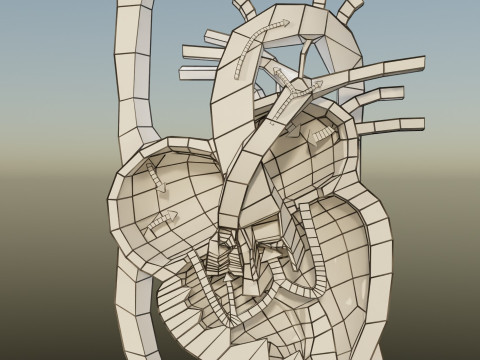

The model meshes include adult circulation versus circulation in Tetralogy of Fallot (TAF), arrow labels and text labels. The blood flow in a patient with Tetralogy of Fallot is outlined in this model. To contrast it to normal blood circulation a separate model of normal circulation is included. The Tetralogy of Fallot (OVER RIDING OF AORTA, PUL STENOSIS, VENTRICULAR SEPTAL DEFECT, RIGHT VENTRICULAR HYPERTROPHY), fossa, ligament teres , venosus, and arteriosus are duly depicted with proper labelling and blood flow directional arrows. Excellent model for teaching, demonstration and knowlegde of human body. The models include both procedural and image textures blend files separately. The texture file include diffuse, roughness and normal png and jpeg based on non overlapping UV maps.

- बहुभुज:285000

- वर्टिसिस:230000